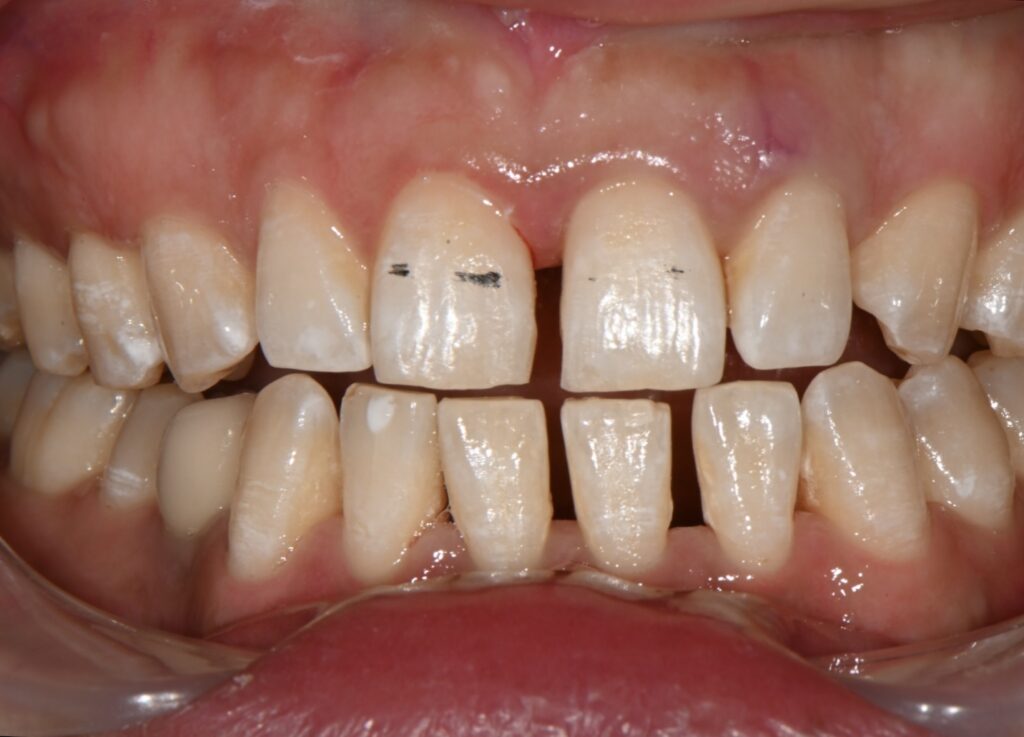

일단은 재치료를 위해서는 기존의 레진을 제거해야 합니다

레진을 제거하고 나면 그 공간이 아마도 더 넓어질 것으로 보입니다

보이는것처럼 레진을 제거하고 난 공간입니다

이 공간을 다시 레진으로 재치료를 해보도록 하겠습니다